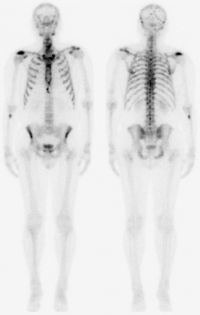

Scintigrafie skeletu

Scintigrafie skeletu.

Planární scintigrafie

Po aplikaci radioindikátoru dochází k jeho distribuci v určitých částech organismu, tuto distribuci pomocí zevní detekce vycházejícího záření γ zobrazujeme scintilační kamerou , v počítači vznikají digitální scintigrafické obrazy, které jednak hodnotíme vizuálně, jednak můžeme pomocí křivek matematicky analyzovat vyšetřované procesy a počítat kvantitativní parametry funkce jednotlivých orgánů.